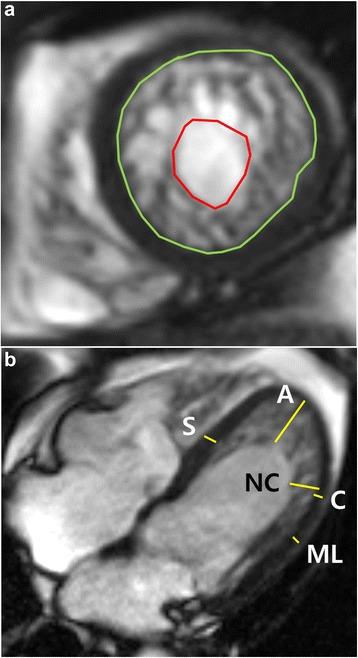

METHODS

This retrospective study included 145 subjects with mild to severe trabeculation of the left ventricle myocardium [24 patients with isolated LVNC, 33 patients with non-isolated LVNC, 30 patients with dilated cardiomyopathy (DCM) with non-compaction (DCMNC), 27 patients with DCM, and 31 healthy control subjects with mild trabeculation]. The left ventricular (LV) ejection fraction, global LV myocardial volume, trabeculated LV myocardial volume, and number of segments with late gadolinium enhancement were measured. In addition, the most prominent non-compacted (NC), compacted (C), normal mid-septum, normal mid-lateral wall, and apical trabeculation thicknesses on the end-diastolic frames of the long-axis slices were measured.

方法

本回顾性研究纳入了145例左心室心肌小梁化程度从轻到重的受试者[24例孤立性LVNC患者、33例非孤立性LVNC患者、30例伴有心肌致密化不全的扩张型心肌病(DCM)患者、27例DCM患者以及31例心肌小梁化程度较轻的健康对照者]。测量左心室(LV)射血分数、左心室整体心肌体积、小梁化左心室心肌体积以及延迟钆增强节段数。此外,还测量了长轴切片舒张末期帧上最突出的非致密化(NC)、致密化(C)、正常室间隔中部、正常室侧壁中部以及心尖小梁厚度。